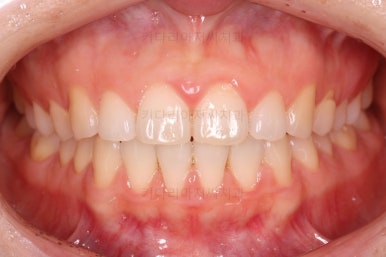

벌써 치료 종료시의 모습입니다.

치료는 총 5개월이 걸렸네요.

일반적으로 부분교정은 6개월 전후로 치료기간이 걸리긴 하고 이번 환자분의 경우는 삐뚤어진 정도가 심한 편이 아니라서 짧게 걸린 편이었어요.

치료결과는 매우 만족하셨습니다.

삐뚤었던, V자로 꺾여있던 나비앞니치아가 가지런해졌어요.

양치질도 훨씬 편해져서 장기적으로 구강건강에도 도웅미 되실 거에요.

다시 틀어지지 말라고 앞니 안쪽에 유지장치를 부착해 주고 마무리를 했습니다.